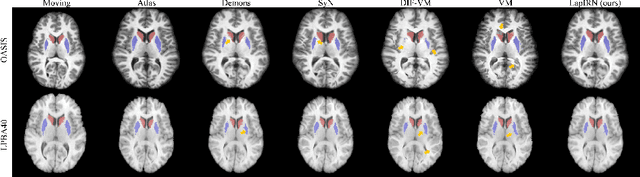

Abstract:Deep learning-based methods have recently demonstrated promising results in deformable image registration for a wide range of medical image analysis tasks. However, existing deep learning-based methods are usually limited to small deformation settings, and desirable properties of the transformation including bijective mapping and topology preservation are often being ignored by these approaches. In this paper, we propose a deep Laplacian Pyramid Image Registration Network, which can solve the image registration optimization problem in a coarse-to-fine fashion within the space of diffeomorphic maps. Extensive quantitative and qualitative evaluations on two MR brain scan datasets show that our method outperforms the existing methods by a significant margin while maintaining desirable diffeomorphic properties and promising registration speed.